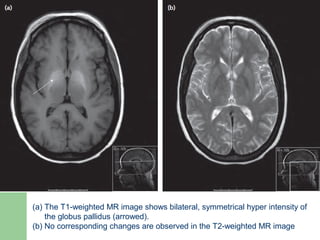

 Cerebral morphology

– T1-weighted hyperintensity of basal ganglia on MRI

 commonly seen in cirrhosis

 correlates best with severity of liver disease

 in part related to brain manganese deposition

 reverses after liver transplantation

(a) The T1-weighted MR image shows bilateral, symmetrical hyper intensity of

the globus pallidus (arrowed).

(b) No corresponding changes are observed in the T2-weighted MR image